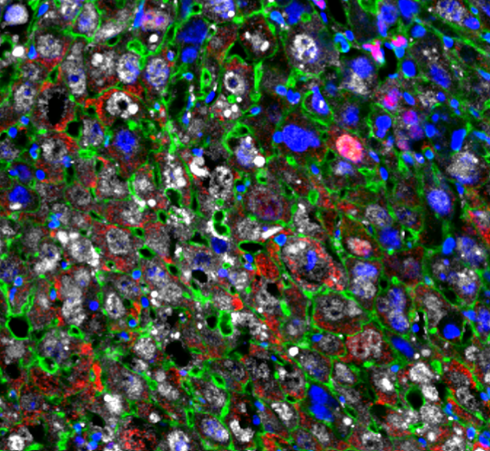

پستانداران معمولاً نمیتوانند اندامهای خود را به اندازه سایر مهرهداران مانند ماهی و مارمولک بازسازی کنند. اکنون، دانشمندان مؤسسه مطالعات بیولوژیکی Salkراهی برای بازگرداندن نسبی سلولهای کبد به حالتهای جوانتر پیدا کردهاند. این نتایج که در مجلهی Cell Reportsدر آوریل 2022 منتشر شد، نشان میدهد که استفاده از مولکولهای برنامهریزی مجدد میتواند رشد سلولی را بهبود بخشد و منجر به بازسازی بافت کبد در موشها شود. این رویکردها را میتوان به جایگزینی کل اندام تعمیم داد. این یافتهها میتوانند به توسعه درمانهای جدید برای عفونت، سرطان و بیماریهای ژنتیکی کبد و همچنین بیماریهای متابولیک منجر گردند. نویسندگان قبلاً نشان دادند که چگونه چهار مولکول برنامهریزی مجدد سلولی- Oct-3/4، Sox2، Klf4و c-Myc، که «عوامل Yamanaka» نیز نامیده میشوند؛ میتوانند روند پیری را کند کرده و ظرفیت بازسازی بافت عضلانی را در موشها بهبود بخشند. در آخرین مطالعه خود، نویسندگان از عوامل یاماناکا استفاده کردند تا ببینند که آیا میتوانند اندازه کبد را افزایش دهند و عملکرد کبد را بهبود بخشند و در عین حال طول عمر موشها را افزایش دهند؟ این فرآیند شامل تبدیل بخشی از سلولهای کبدی بالغ به حالتهای «جوانتر» است که باعث رشد سلولی میشود.مسئلهای که بسیاری از محققان در این زمینه با آن روبرو هستند این است که چگونه بیان عوامل مورد نیاز برای بهبود عملکرد سلولی و جوانسازی را کنترل کنند؛ زیرا برخی از این مولکولها میتوانند باعث رشد بیرویه سلولی از جمله سرطان شوند. در واقع عوامل یاماناکا شمشیر دو لبه هستند. از یک طرف، آنها پتانسیل افزایش بازسازی کبد در بافت آسیبدیده را دارند؛ اما از طرفی میتوانند باعث ایجاد تومور شوند. برای دور زدن این موضوع، یک تیم تحقیقاتی از پروتکل کوتاهمدت فاکتور یاماناکا استفاده کردند که در آن موشها تنها یک روز تحت درمان قرار گرفتند. دانشمندان در حین مطالعه این مکانیسم برنامهریزی مجدد، به کشف دومی دست یافتند. ژنی به نام Top2aدر برنامهریزی مجدد سلولهای کبدی نقش دارد و یک روز پس از درمان کوتاه مدت فاکتور یاماناکا بسیار فعال است. هنگامی که محققان ژنی را که سطح توپوایزومراز 2aرا کاهش میداد مسدود کردند، شاهد کاهش 40 برابری در نرخ برنامهریزی مجدد سلولی بودند که منجر به سلولهای جوان بسیار کمتری شد. نقش دقیقی که Top2aدر این فرآیند ایفا میکند، حوزه تحقیقاتی آینده است. هنوز کار زیادی باید انجام شود تا بتوانیم اساسمولکولی زیربنای رویکردهای برنامهریزی جوانسازی سلولی را درک کنیم. این یک نیاز ضروری برای معکوس کردن اثرات بیماریهای انسانی است. منبع: